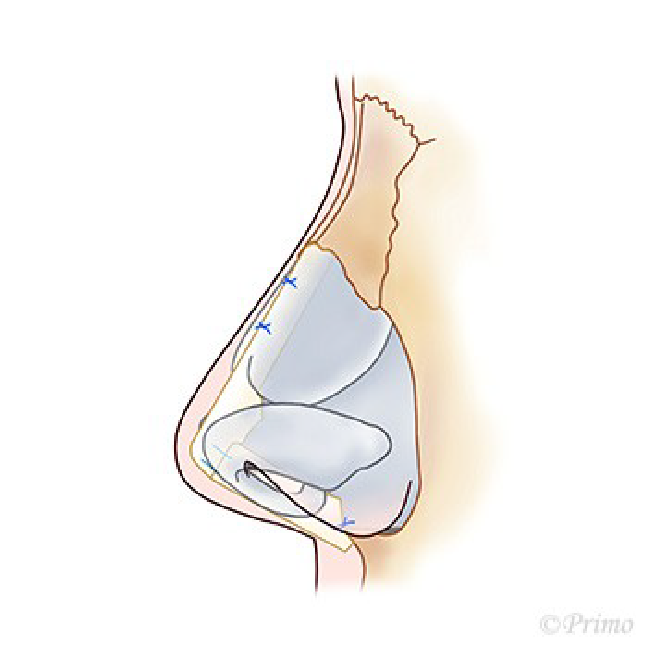

手術は鼻の穴の中からすべて行います。傷は表面上わかりません。鼻翼軟骨の余分な脂肪部分を除去し、さらに鼻翼軟骨の上側を切除します。

その方の鼻の皮膚の厚さや軟骨の大きさにより、軟骨の縫合、移植術をおこないます。ただ寄せあうだけで細くすると、Pollybeak変形といわれる、正面からは細くても、横からの形態が丸い形になりがちです。この変形を予防するため、鼻翼軟骨の上側を切除した部分を先端に移植し、鼻の横からのプロフィールをさらに改善するように軟骨移植をおこないます(3次元的形成)。

これにより、正面からも、横からも鼻がほっそりと綺麗に仕上がります。手術は約1時間30分で終了します。術後3~5日ほどギプスを固定いたします。

単純に細くするだけでは、Pollybeak変形になりやすくなります。矢印の部分が盛り上がる変形がPollybeak変形です。Pollybeakはオオムのくちばしという意味です。

鼻翼軟骨(シルバーの部分)が鼻先の形体を形成します。

鼻翼軟骨の上部(水色の部分)を切除し、中央の赤い線で鼻翼軟骨を切断します。

切断した部分から上を反転させ、鼻先に突出させます。

先ほど切除した水色の部分の軟骨を、軟骨と軟骨の間に挟み込み、鼻の柱として用います(水色の部分)。

水色の部分のもう一枚を、鼻先の両サイドに固定し、鼻先を補強します(水色の部分)。この鼻翼軟骨移植法を行うことで、正面からもほっそりと、横からもシャープなかっこいい鼻先にすることがでます。